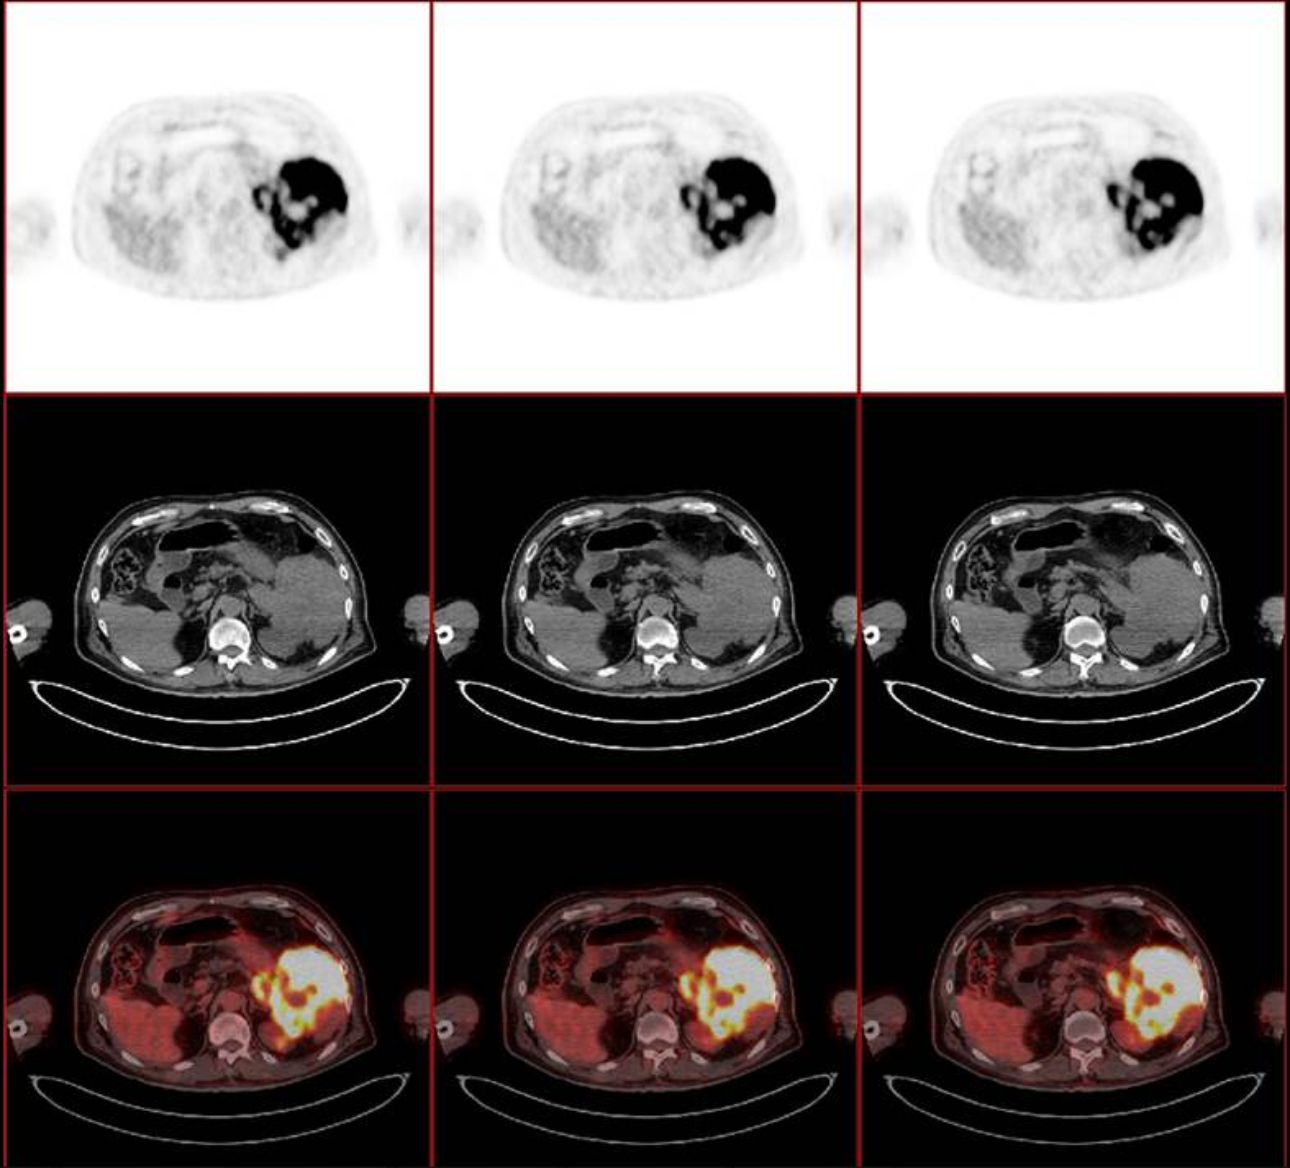

환자는 혈액내과에서 R-Hyper-CVAD-A 화학요법을 받았으며 연속된 CT 사진을 통해 종양 크기가 현저히 감소한 것을 확인 할 수 있습니다. (Fig 4 A-C). 환자의 전반적인 상태도 또한 상당히 좋아졌습니다.

형상4. 연속된 CT에서 종괴 크기의 감소 관찰됨(A) 치료 전 (B) 항암화학요법 1개월 후, (C) 항암화학 요법 2개월 후